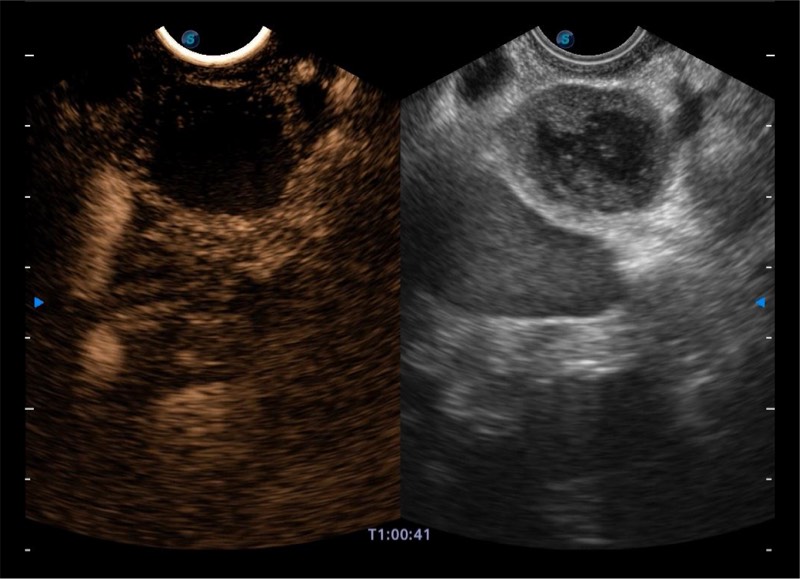

基于二十年的超声技术积累,九州酷游提供了最新一代的独立超声主机,在提供高质量图像的同时满足多学科使用。具备常见多普勒技术并提供弹性成像、声学造影等高端影像技术。新一代传感器具有更强的抗干扰能力并减少图像伪影。

4-12MHZ宽频输出